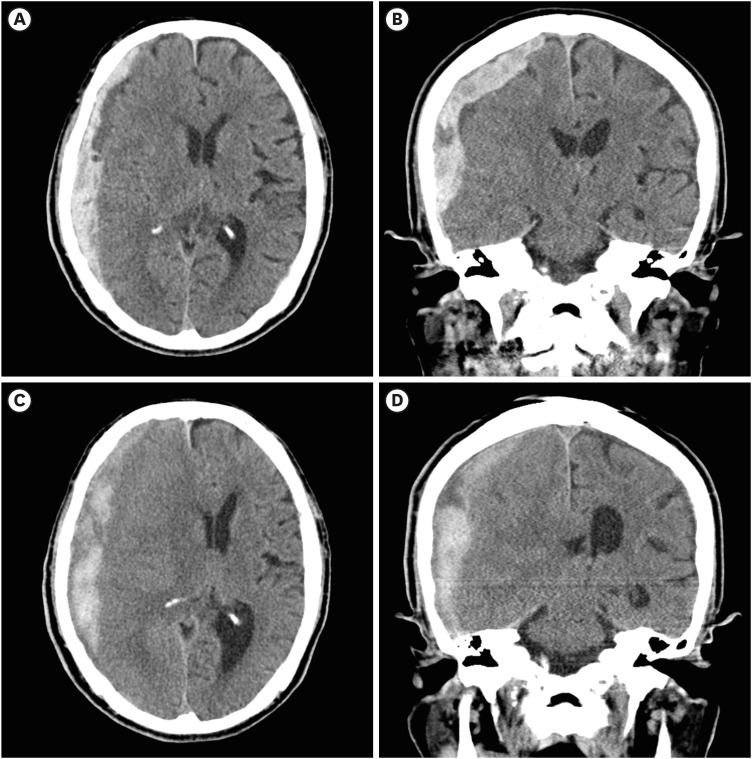

本文报告一位89岁的亚急性硬膜下血肿(SDH)患者,通过钻孔穿刺(BHT)和硬膜下引流放置局部麻醉治疗,随后使用纤维蛋白溶解剂组织纤溶酶原激活剂(tPA)液化血肿。最初,患者表现为急性创伤后SDH,无神经系统症状,给予保守治疗。大约一周后,患者出现偏瘫并进展为昏迷状态。影像学证据显示亚急性SDH已演变为慢性阶段,肿块效应增加,导致新的神经功能缺损。虽然考虑开颅手术,但在护理人员的要求下没有进行全身麻醉。BHT后,放置硬膜下导管,但最初的引流很少。然后给予tPA以促进液化和排水。脑部后续电脑断层扫描证实血肿有明显引流。患者随后恢复意识和运动功能。本报告讨论了一种微创治疗亚急性SDH的方法。我的方法是结合BHT和纤溶治疗,使用tPA,以最小的手术干预有效地清除血肿。在这里,我提出了一个使用tPA的病例,详细介绍了纤维蛋白溶解治疗的方法、影像学发现和临床结果。

This report presents an 89-year-old patient with subacute subdural hematoma (SDH) treated with local anesthesia via burr-hole trephination (BHT) and subdural drain placement, followed by liquefaction of the hematoma using the fibrinolytic agent, tissue plasminogen activator (tPA). Initially, the patient presented with acute post-trauma SDH without neurological symptoms, for which conservative treatment was administered. About a week later, the patient developed hemiplegia and progressed to a stuporous state. Radiographic evidence indicated that the subacute SDH had evolved into a chronic stage with an increased mass effect, causing new neurological deficits. Although craniotomy was considered, general anesthesia was not performed at the caregiver's request. After BHT, a subdural catheter was placed, but initial drainage was minimal. tPA was then administered to promote liquefaction and drainage. Follow-up computed tomography of the brain confirmed significant drainage of the hematoma. The patient subsequently recovered consciousness and motor function. This report discusses a less-invasive alternative for managing symptomatic subacute SDH. My approach of combining BHT with fibrinolytic therapy using tPA facilitated effective evacuation of the hematoma with minimal surgical intervention. Here, I present a case where tPA was used, detailing the methodology, imaging findings, and clinical outcomes of fibrinolytic therapy.